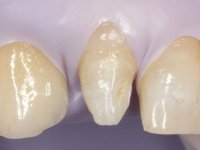

• Restoration of teeth Superior Central Incisors with feldspathic ceramic veneers.

This addition of resin would guide the ceramist in the final placement of the gingival tonality ceramic. The crown that would rehabilitate tooth 1.3 was cemented in this test session with glass ionomer cement, reinforced with composite resin. Once the laboratory work was finished on the veneer for tooth 1.2, the abutment, and the veneer for the implant, this was bonded in the mouth, after placement of the absolute insulation. The work completely satisfied the patient. For eight years, the patient had periodical check-ups, and was pleased with the treatment, but also began to show interest in an aesthetical intervention on the upper central incisors. Once the second phase of our intervention was decided, dental preparation of teeth 1.1 and 2.1 was performed for the placement of two feldspathic veneers. Particular care was taken in the distal inter-proximal preparation adjacent to the abutment of the implant.

The axis of insertion of the veneer in relation to the abutment was very carefully evaluated. The feldspathic veneers were prepared in the laboratory and then bonded to the mouth after placing absolute insulation. One year later, we began our third phase of treatment, after the veneer in tooth 2.1 fractured. A dental preparation was done on the bonded veneer, seeking to extend the distal inter-proximal interface more to the palate. The objective would be to move the veneer to a more palatine contact point. Preparation of tooth 1.2 was limited to creating an insertion axis. After preparation, the total crown and laboratory veneer were bonded to the mouth. First, the crown was bonded using a relative insulation with Teflon, later the veneer was bonded after the absolute insulation placement. In the crown, I used this type of insulation to avoid the use of staples. It would be difficult to apply due to the shape and size of the tooth, and would also be aggressive to the soft tissues. After bonding procedures, the occlusal integration of the work was evaluated.